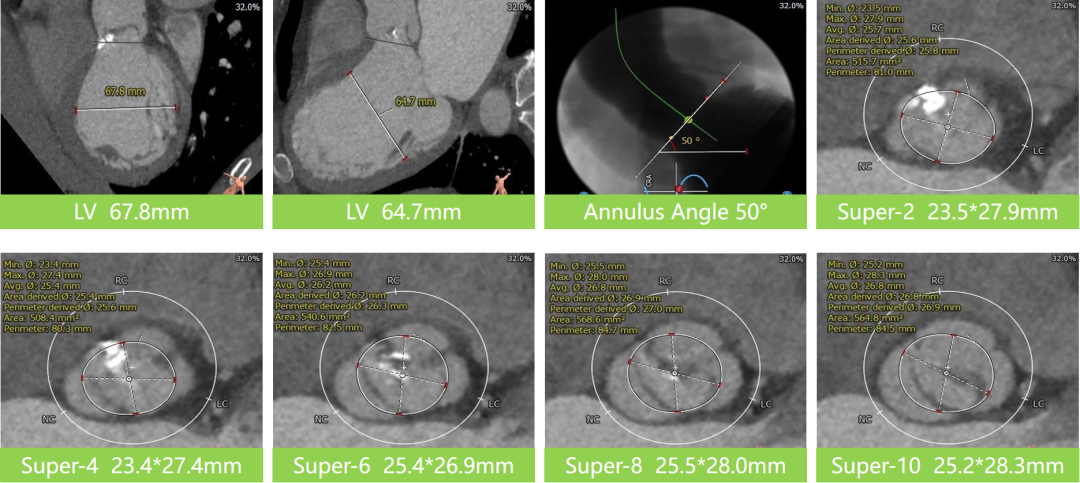

主动脉根部评估

瓣上分析&心室大小分析

• 三叶式主动脉瓣,轻度钙化,钙化主要分布在右无交界,敞口型流出道,人工瓣膜锚定难度高,存在向上或向下位移风险,采用右窦中心体位,瓣环下2-4mm进行初始释放;

• 根据根部及瓣上分析,该患者钙化不重,瓣口较大,采取不预扩,直接植入TaurusElite AV31型号瓣膜策略,瓣膜释放后观察形态,必要时采用25mm球囊进行后扩;